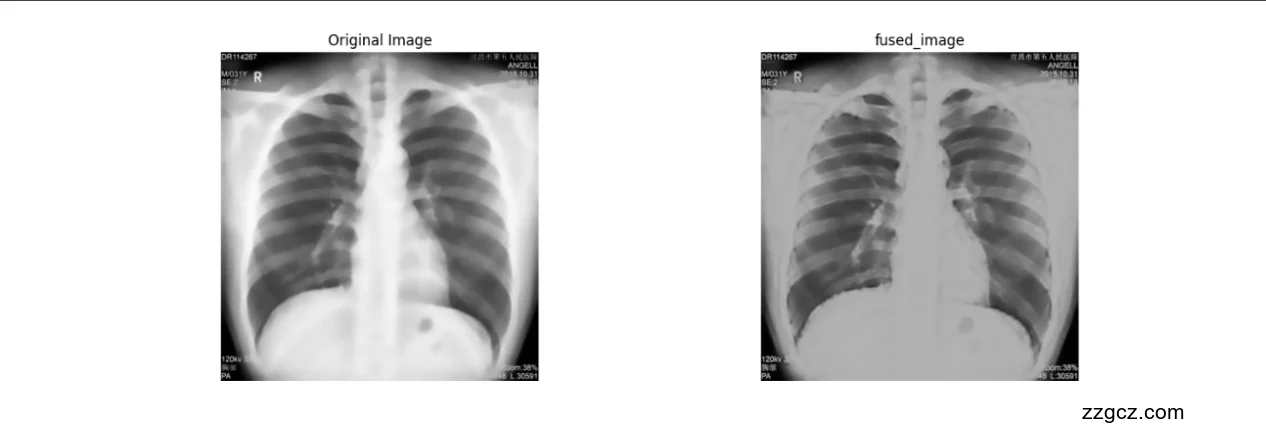

功能描述:图像融合模块是本研究中用于增强尘肺胸片可读性的关键部分,其主要任务是将Canny边缘检测算法得到的边缘图与CLAHE算法处理后的图像进行有效融合。该过程旨在突出显示胸片中的关键特征,特别是那些可能指示早期尘肺病变的微妙区域。通过这种融合技术,我们能够在保持图像自然外观的同时,增强对病理特征的识别,从而为医生提供更为精确的诊断信息。

融合技术:在实施图像融合时,采用了加权融合技术,这种方法考虑到了边缘检测图像与CLAHE处理图像的相对重要性。加权融合技术通过为每个像素点分配一个权重系数,根据其在边缘图和CLAHE图中的强度,优化了图像中边缘和细节的显示。这不仅提高了图像的对比度和清晰度,还确保了重要医学信息的最大保留,特别是在显示尘肺特有的小结节和纤维化区域方面具有显著优势。此外,加权融合技术允许调整融合参数,以适应不同的图像特点和诊断需求,使得每一幅胸片的处理都能够最大限度地反映其病理特征。

不仅增强了图像的视觉效果,还改善了图像的解释性,这对于早期诊断尘肺疾病至关重要。此外,优化显示的边缘和详细信息有助于医生更好地识别和分析尘肺的早期迹象,如肺部的微小改变和不规则纹理,这些可能在常规检查中被忽视。整体而言,图像融合模块通过技术上的创新,为尘肺的早期检测和治疗提供了强有力的视觉支持。

不仅展示了原始胸片与处理后图像的差异,而且通过视觉对比直观地展示了融合图像的效果,从而评估图像处理算法的改进效果。

输出方面,该模块具备两项主要功能:首先,它能在用户界面上同时显示原始和处理后的图像,这样做不仅便于比较和评价CLAHE融合边缘增强算法对图像质量的提升,还可以详细观察算法对图像细节的改进。通过这种对比,医生和放射科技师可以直观地评估处理后图像在揭示肺部细节方面的优势,特别是在识别通常难以观察的微小病变和纤维化结构上。